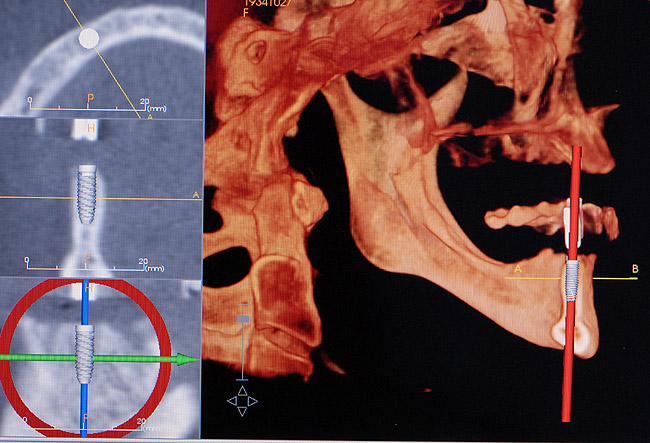

Figure 9  A computed tomography scan can provide additional information to aid the implant team for proper placement of the implant(s).

Figure 9

Patient expectations remain extremely critical. The treatment options must be able to meet these expectations, otherwise tooth replacement of the edentulous area with dental implants should not be attempted. A set of mounted casts in centric relation with a full contour diagnostic wax-up, including the hard- and soft-tissue deficits, is mandatory prior to initiating treatment. This is beneficial in accessing the edentulous space and communicating the information concerning the edentulous defect with the laboratory technician, the implant surgeon, and most importantly, the patient. In addition, CBCT can also be extremely helpful in diagnosing the edentulous site 3-dimensionally and providing vital information to the surgeon prior to implant placement (Figure 9). Only after the diagnosis and treatment plan is fully understood by all parties should the treatment be initiated. In many situations, hard- and soft-tissue grafts are necessary in order to reconstruct the edentulous site as near to its original contours as possible (Figure 10 through Figure 12). This will significantly enhance proper positioning of the implant for prosthetic needs and help to increase the prognosis for an esthetic result.27 At the time of implant placement, a surgical template should be used to help ensure that the implant is placed in the proper position. The surgical template can be fabricated from the diagnostic wax-up or generated from planning software using the Digital Imaging and Communications in Medicine data obtained from the CBCT. The esthetic result is generally dictated at the time the implant is placed, hence the need for such a detailed assessment.